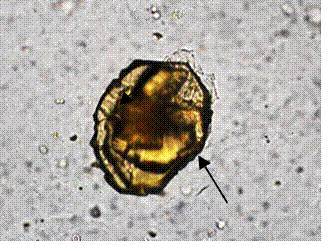

3、箭头所指细胞内结构的名称:胆红质结晶

| 胆红质结晶 |